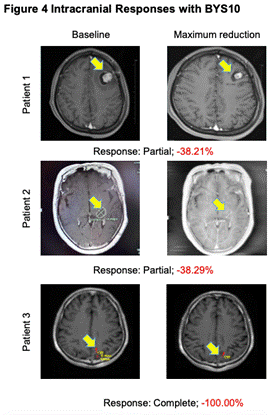

高效入腦:BYS10治療伴腦轉移RET突變實體瘤實現(xiàn)顱內(nèi)緩解

研究人員在4例至少有1個可測量顱內(nèi)病灶(1例顱內(nèi)完全緩解)的患者中觀察到顱內(nèi)抗腫瘤活性。

圖4.顱內(nèi)抗腫瘤活性

從本次ASCO大會所公布的高選擇性RET抑制劑BYS10公布了首項Ⅰ/Ⅱ期人體研究結果來看,BYS10在RET實體瘤治療領域具有非常大的潛力:首先,安全性結果充分表明,BYS10治療RET突變實體瘤的安全性良好,3-4級TRAE及嚴重不良反應的發(fā)生率低,利于患者長期管理。其次,初步療效數(shù)據(jù)結果顯示,患者治療后的ORR為62.5%,DCR為85%,這表明近三分之二的患者經(jīng)過BYS10治療能夠有效實現(xiàn)疾病緩解,超過五分之四的患者能夠實現(xiàn)疾病控制,尤其TC和MTC患者的DCR可達到100%。在臨床上更為常見的NSCLC患者中,BYS10治療的ORR能夠達到60%,DCR能夠達到80%,充分展現(xiàn)了BYS10的治療潛能。此外,對于臨床上十分關注的腦轉移患者,經(jīng)BYS10治療后可實現(xiàn)顱內(nèi)病灶的有效緩解,證實了BYS10的顱內(nèi)病灶控制潛能。